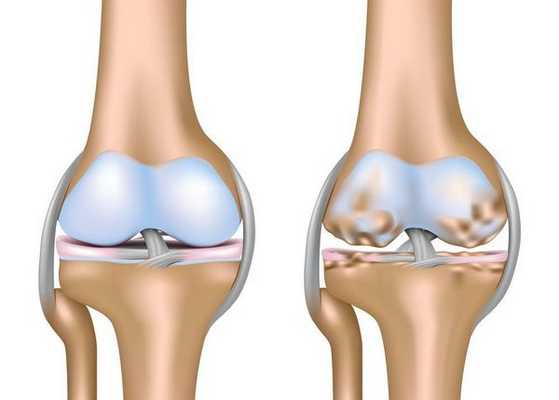

Сустав — механизм подвижного соединения костей, в котором их окончания сходятся в суставной сумке. Суставные окончания костей покрывает упругий тонкий слой гиалинового хряща, не содержащий нервных окончаний и кровеносных сосудов. При различных движениях хрящ выполняет роль амортизатора, уменьшая давление на сочленяющиеся поверхности костей и обеспечивая их плавное скольжение друг относительно друга.

Кости суставов скрепляются между собой связками и сухожилиями, которые действуют как сильные гибкие кабели и позволяют совершать движение в нужных направлениях. Они полностью окружены капсулой сустава. Капсула сустава выложена тонкой синовиальной оболочка, которая вырабатывает смазочную жидкость в пространство сустава. Смазочная жидкость обеспечивает питание гиалинового хряща и является надежной смазкой суставных концов костей. Воспаление синовиальной оболочки (синовит), кровоизлияния в полость сустава (гемартроз) способствуют развитию дегенеративно-дистрофических и воспалительных процессов в суставе.

Первое существенное изменение при остеоартрозе – смягчение и образование ямок на гладкой поверхности хряща. По мере прогрессирования артрита слой хряща, покрывающий суставные поверхности, становится все тоньше, вплоть до полного разрушения, оставляя незащищенными концы костей.

Без нормальной скользящей поверхности становится болезненным и трудным двигать суставом. Поскольку хрящ продолжает разрушаться, по краям сустава формируются костные выросты, как бы компенсирующие потерю хряща за счет увеличения суставных поверхностей. Это является причиной деформаций суставов (сустав теряет свою форму) при артрите. В народе подобное состояние называют "отложение солей", что является просто неграмотным названием артроза.